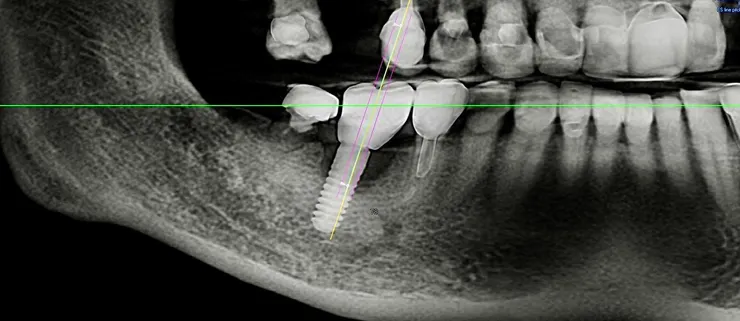

但人工植牙少了這一層天然保護,當患者咬合時產生的應力就會直接傳導到植體與齒槽骨之間,長期下來可能會造成植體周圍的骨組織吸收,進而出現 骨質流失(bone loss) 的情形。

尤其對於本身已有骨質疏鬆體質、或喜歡吃堅果、魷魚絲等較硬食物的患者,傳統的全瓷冠或全鋯冠等高硬度、零彈性的植牙假牙,其實隱藏著不小的風險。

這些材質雖然美觀耐磨,卻不具備任何避震能力,長期使用可能導致植體過早失敗。

最大特色是它的 彈性模數(Elastic Modulus)接近齒槽骨,這代表它能像天然牙周韌帶一樣,在咬合時發揮「避震器」的作用,有效分散咬合壓力,減少骨組織的直接衝擊。這樣不僅能保護植體周圍骨頭,也有助於延長植體的壽命。